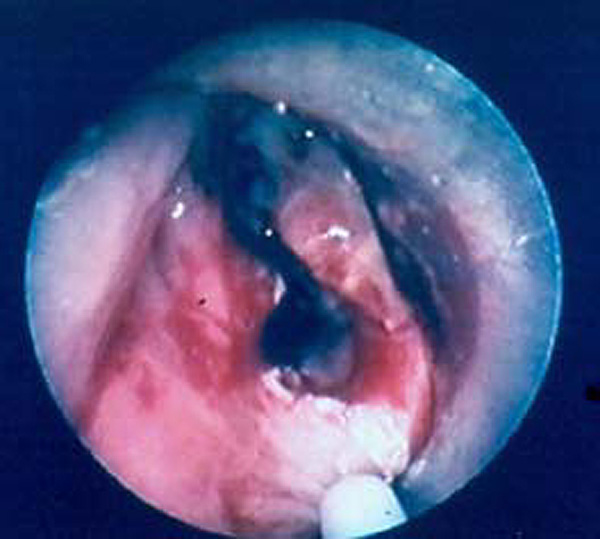

- Vascular compression

Patients with postintubation tracheal stenosis are occasionally good candidates for airway dilation and stenting, but in most of these patients surgical resection and reconstruction should be performed [7,8]. In patients who are candidates for resection and reconstruction only temporary endoscopic palliation should be considered in preparation for surgery to allow adequate stabilization of the inflammatory lesion [9]. Tracheobronchial stenting should be advocated only for patients with an extremely high surgical risk (always consider that tracheal resection is a neck operation with a relatively low surgical insult), for patients refusing surgery, or for patients with a long stenosis that is not amenable to surgical correction. Some rare benign conditions are appropriate for stenting, including anastomotic stenosis after tracheal and bronchial sleeve resection, inflammatory or infectious conditions causing airway stenosis, vascular compression, and tracheobronchial malacia. Patients undergoing lung transplantation might also benefit from endobronchial stenting if airway complications such as bronchial stenosis or anastomotic dehiscence occur (Figure 3).